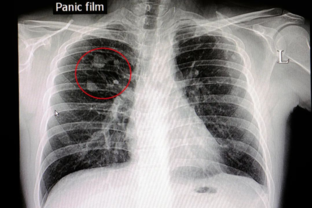

Что об этих образованиях говорит западная медицина и почему китайская медицина их относит к болезням вызванным влагой, сыростью, "мокротой" . в первой части статьи засматривались узелки в щитовидке, легких и западный подход к лечению Гиперплазия молочной железы С точки зрения западной медицины, подавляющее большинство случаев гиперплазии молочной железы является нормальным физиологическим явлением и доброкачественным поражением. Точно так же как и менструальные боли - нам с детства говорили, что это нормальное явление, надо потерпеть...